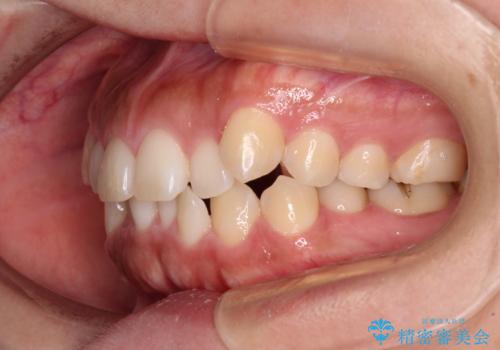

カリエールディスタライザーを併用したことで、すっきりとした口元になり、上下の正中を合わせることができました。